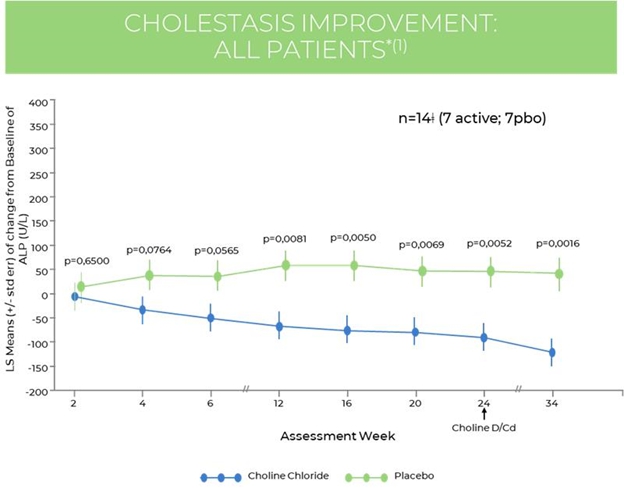

At baseline, LS mean ALP concentration was 239.3 ± 118.93 in the IV Choline Chloride group and 148.1 ± 100.2 in the placebo group. The mixed model for repeated measures, or MMRM, analyses demonstrated statistically significant decreases in ALP concentrations at Week 12 (p = 0.008), Week 16 (p = 0.005), Week 20 (p = 0.007), and Week 24 (p = 0.005) for the IV Choline Chloride group, demonstrating a reduction in cholestasis. A trend towards significance was observed at Week 4 (p = 0.076) and Week 6 (p = 0.056). At Week 34, 10 weeks after discontinuation of IV Choline Chloride treatment, LS mean change from baseline in ALP concentrations still demonstrated statistically significant decreases (p = 0.002), demonstrating a significant improvement in cholestasis with treatment with IV Choline Chloride (Figure 4).

In the subgroup of subjects with ALP concentration > 1.5x upper limit of normal (ULN) at baseline, (n=7), mean values at baseline were comparable between the IV Choline Chloride and placebo groups (294.20 ± 87.947 versus 277.00 ± 128.693, respectively). In the sub-group analysis, improvement in ALP was consistent and substantial, with 20-30% improvement over 12-24 weeks of treatment. Statistical significance was observed at 12, 16, and 20 weeks.

Figure 4. Improvement in Cholestasis1: All Patients

| 1 | Protara Therapeutics re-analysis of patient CRF’s, data on file. |

| * | MMRM method used for imputation. |

| ǂ | A placebo subject was excluded from all analyses due to likely IV contrast-induced imaging abnormalities, confirmed by independent radiologist in subsequent re-analysis. |